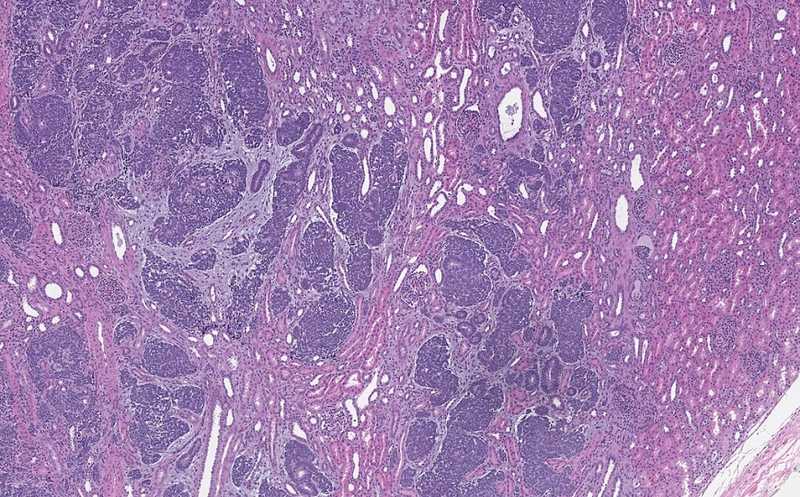

Авторы новой статьи анализировали образцы опухоли Вильмса (нефробластомы). Эта агрессивная эмбриональная опухоль происходит из развивающихся тканей почек. Опухоль Вильмса — самое распространенное злокачественное новообразование мочеполового тракта у детей, которое обычно развивается в возрасте до 5 лет с одинаковой частотой у мальчиков и девочек.